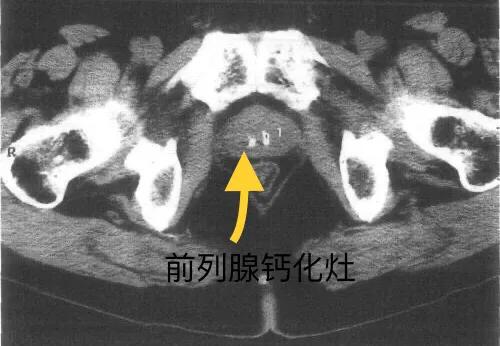

CT检查诊断前列腺钙化灶也比较清楚明确。

前列腺结石就是常说的前列腺钙化灶,B超超声检查显示前列腺内有较小的单发或者多发的强回声。